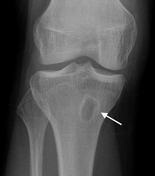

What is a Brodie’s abscess?

Area of walled-off infection in bone

Surrounded by a rim of sclerotic bone (similar to osteoid osteoma - can be difficult to differentiate between the two!)